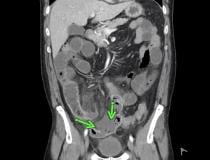

This photo gallery shows the variety of radiological presentations of COVID-19 (SARS-CoV-2) in medical imaging, including computed tomography (CT), radiograph X-rays, ultrasound, echocardiograms and magnetic resonance imaging (MRI). The radiology images show examples of typical COVID pneumonia in the lungs and the numerous complications the virus causes in the body in multiple organs, including the brain, kidneys, heart, abdomen and vascular system.

Ultrasound, especially hand-held ultrasound imaging devices, have become a primary imaging modality for novel coronavirus because of the ease to bag the device and sterilize it after use. CT and mobile X-ray systems are also used as front-line imaging systems for COVID-positive or suspected COVID patients.